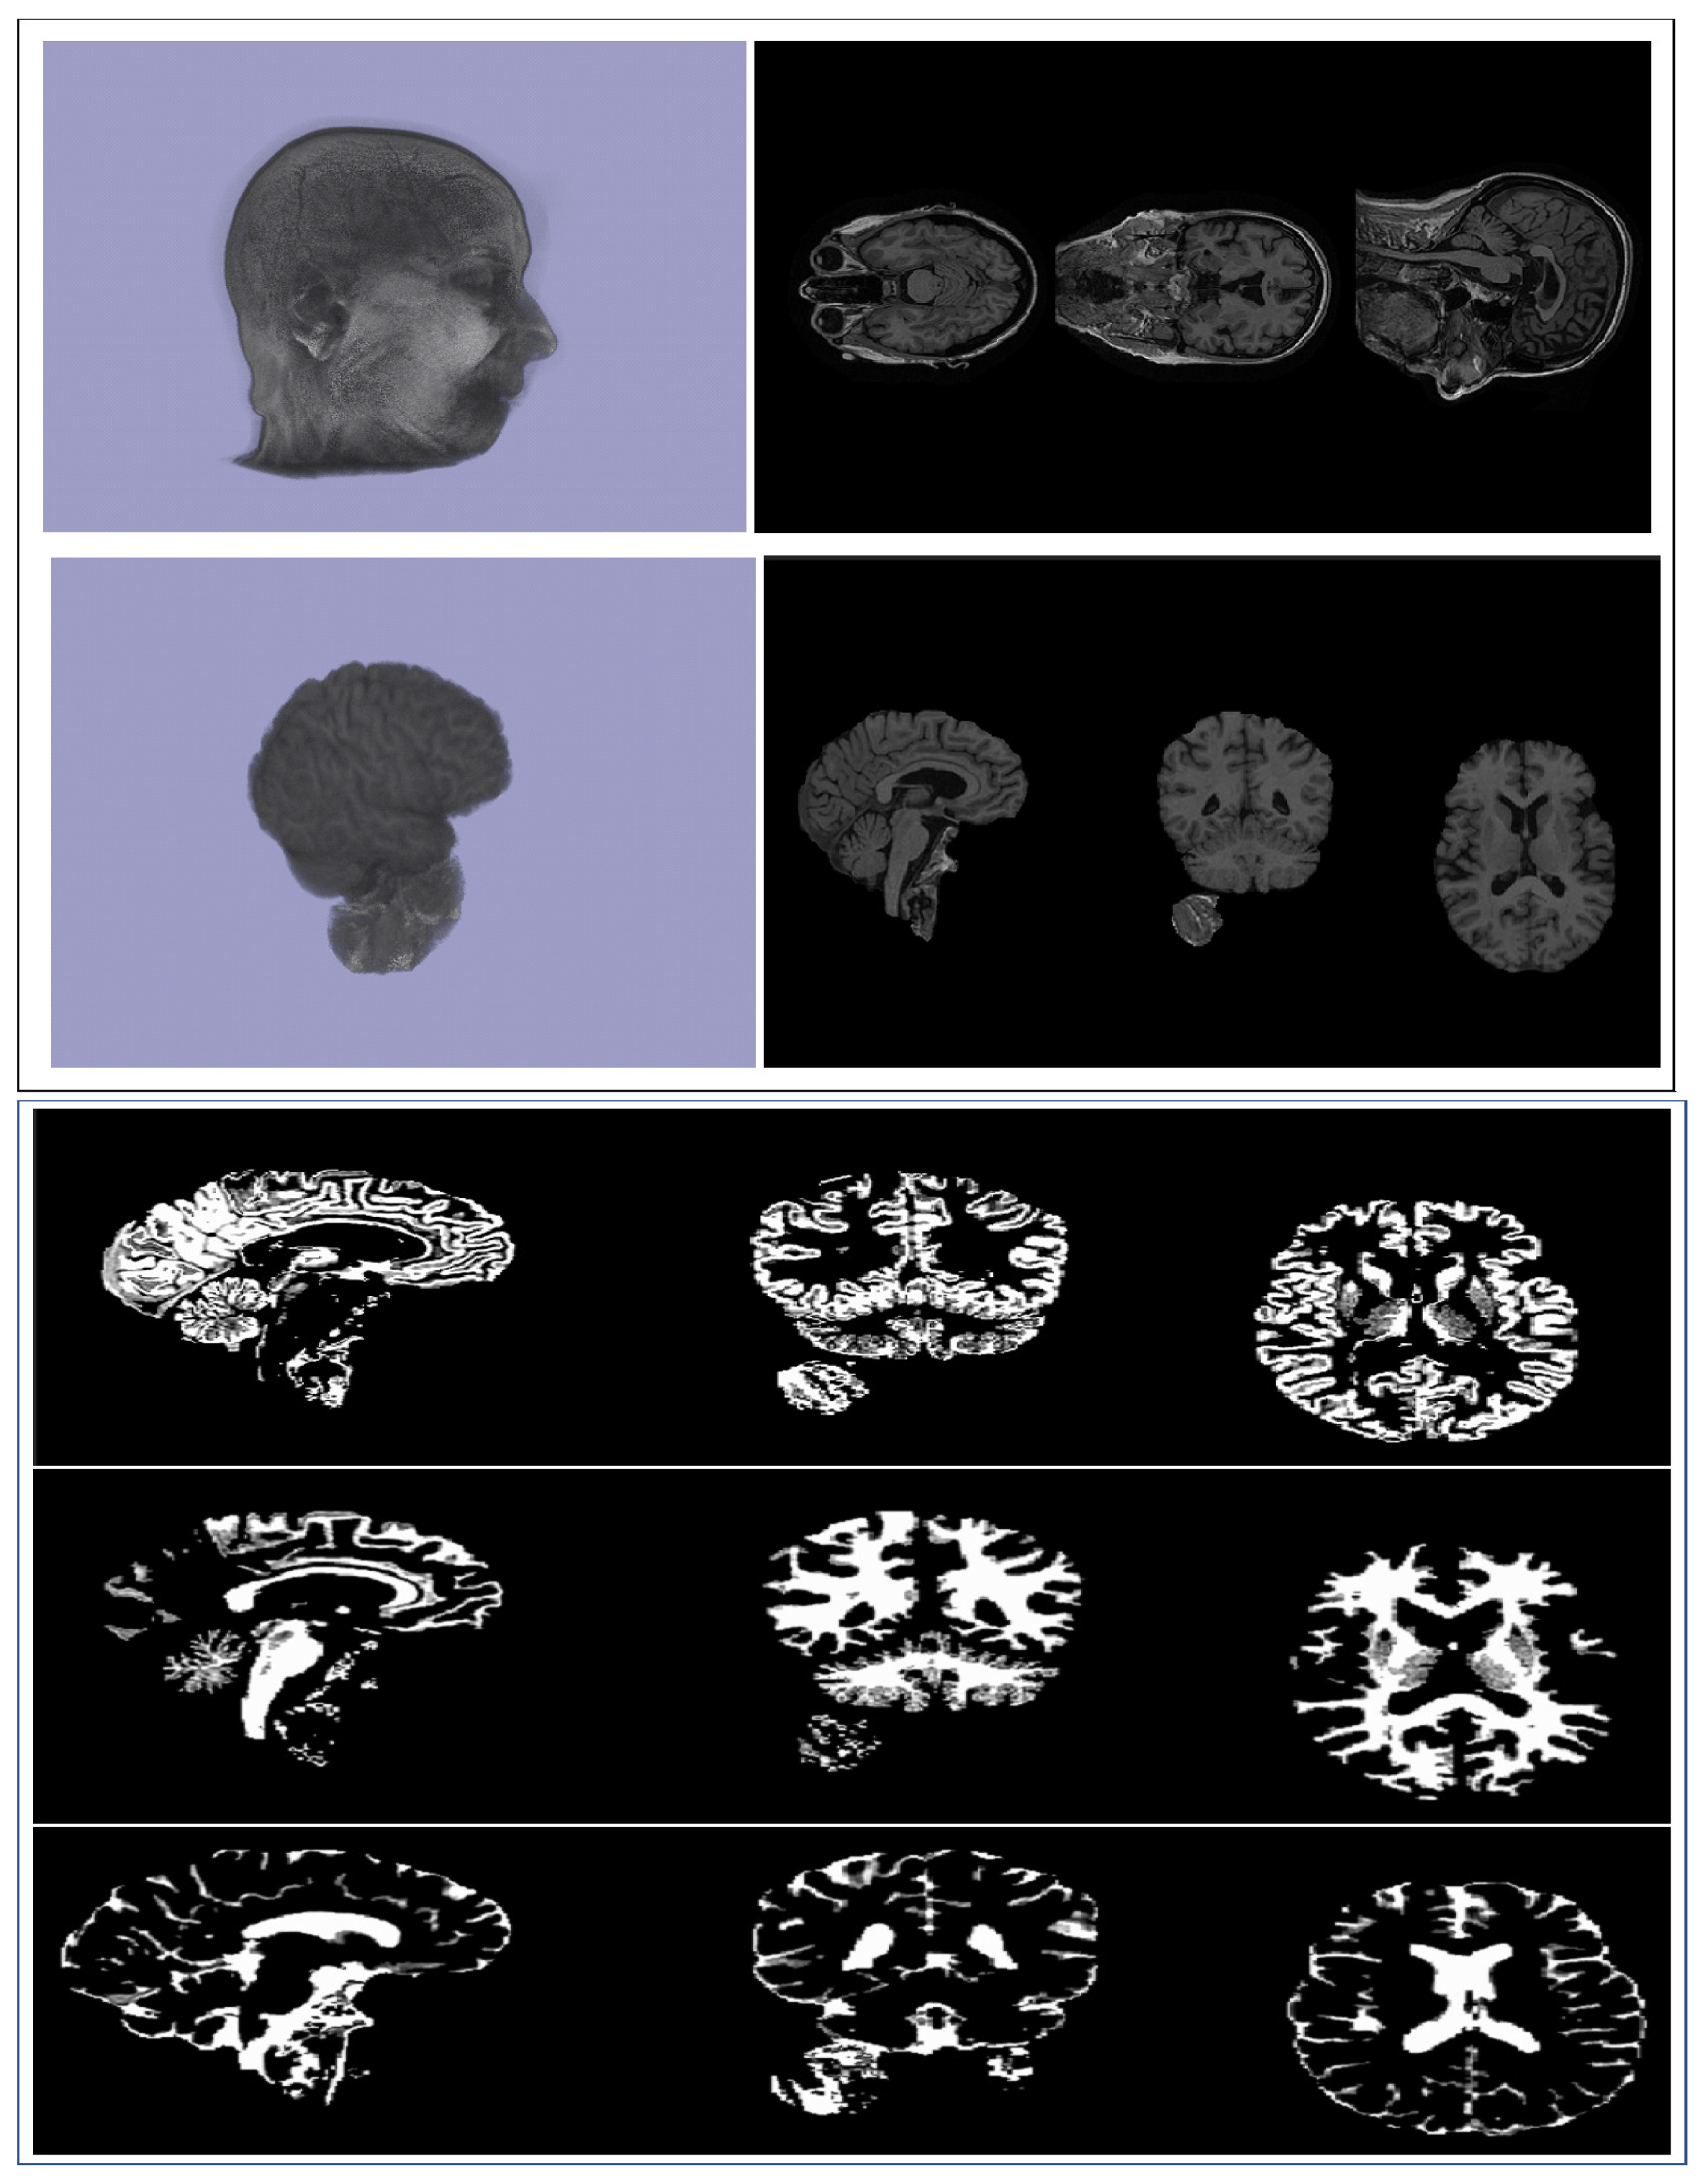

2. Data

Preprocessing and Description